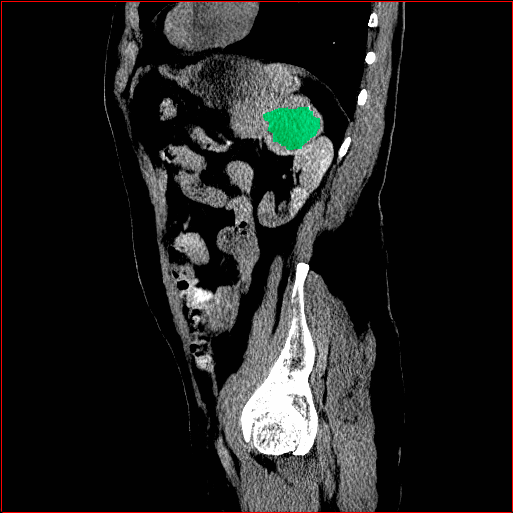

Figure 3 shows the generalizability of MAISI-v2 ControlNet for different body regions and voxel sizes. Figure 4 shows qualitative results for MAISI-v2 ControlNet on 5 types of tumors.

Lung Tumor

0.75×0.75×0.60.75\times 0.75\times 0.6

mm

512×512×512512\times 512\times 512

Liver Tumor

0.75×0.75×0.50.75\times 0.75\times 0.5

512×512×768512\times 512\times 768

Panc. Tumor

1×1×11\times 1\times 1

Colon Tumor

0.75×0.75×1.50.75\times 0.75\times 1.5

512×512×256512\times 512\times 256

Bone-Les

1×1×1.31\times 1\times 1.3

512×512×384512\times 512\times 384

Figure 4: MAISI-v2 segmentation-guided results for five types of tumors. We show results for different voxel spacing and volume size to demonstrate the flexibility of MAISI-v2. Different Hounsfield Unit window is used to better show the contrast between tumor and normal tissues.